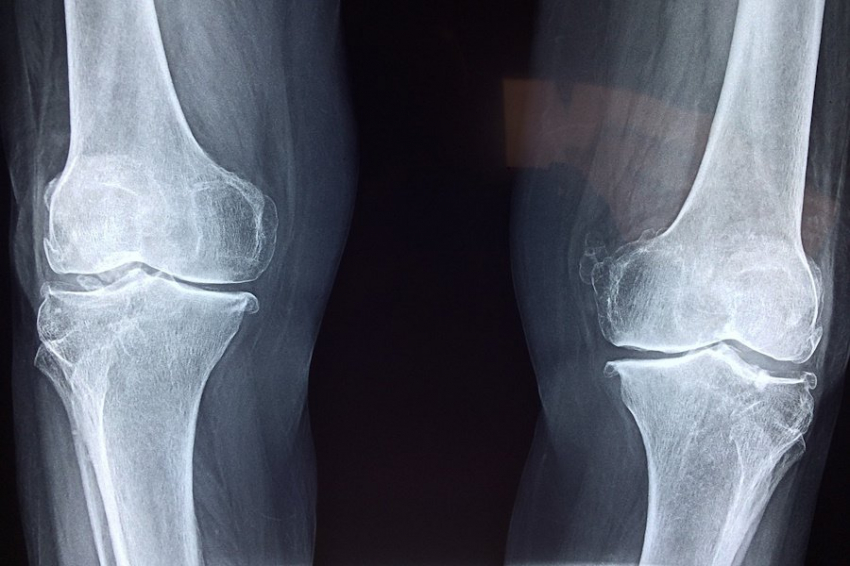

Ученые из Московского физико-технического института (МФТИ) и Института физики металлов Уральского отделения РАН разработали инновационные молды для выращивания сфероидов — трехмерных клеточных структур, которые открывают новые горизонты в восстановлении хрящевой ткани после операций на коленном суставе, сообщает ТАСС.

Сфероиды представляют собой клеточные образования, которые вживляются в поврежденный участок хряща. Они выделяют биологически активные вещества, способствующие регенерации, стимулируя рост новых клеток и их превращение в полноценные хрящевые ткани. Благодаря этим свойствам сфероиды становятся ключевым инструментом в восстановлении суставов после хирургического вмешательства.